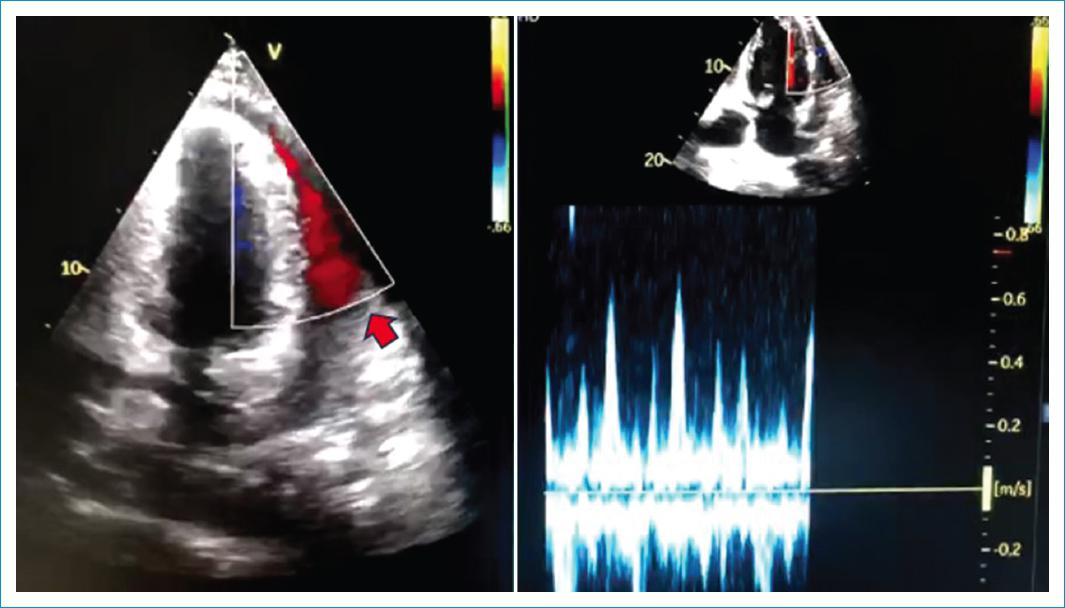

Paciente de sexo masculino, de 49 años, sin antecedentes patológicos, quien consultó por cuadro clínico de quince días de evolución, caracterizado por picos febriles recurrentes, con deterioro de su clase funcional, asociado a dolor torácico, pérdida de la fuerza en miembros inferiores y posterior alteración del estado de consciencia. Al examen físico cardiovascular, se evidenció soplo holosistólico mitral, por lo cual se ordenó un ecocardiograma transtorácico en el que se halló vegetación en la válvula mitral, con perforación del segmento A3 con jet de insuficiencia mitral grave y perforación del anillo mitral anterior con relación al segmento A3, ocasionando una fístula ventrículo-pericárdica con evidencia de derrame pericárdico circunferencial grave y presencia de flujo por Doppler color (Fig. 1; flecha amarilla), en la cavidad pericárdica con signos de taponamiento cardíaco (Fig. 2; flecha roja); ventrículo izquierdo hiperdinámico con fracción de eyección del 68%. Se realizó procedimiento quirúrgico para la resección de la vegetación y la confirmación del trayecto fistuloso con cierre de este usando parche de pericardio autólogo más reemplazo de válvula mitral con prótesis biológica # 27. El paciente tuvo una evolución satisfactoria. El ecocardiograma de control previo al egreso mostró prótesis biológica en posición mitral, normofuncionante (Fig. 3; círculo amarillo), sin fuga periprotésica ni evidencia de fistula residual (Fig. 3), con ventrículo izquierdo de grosor y cavidad normal, hipocinésica global y disfunción sistólica leve (FEVI 40%).